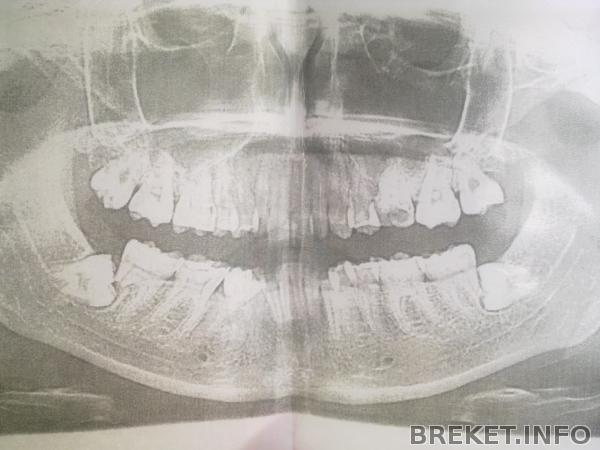

Я постоянно тут переживаю про резорбцию корней семерок. Не отличусь и в этой записи.

Вон она, "красота" моя -